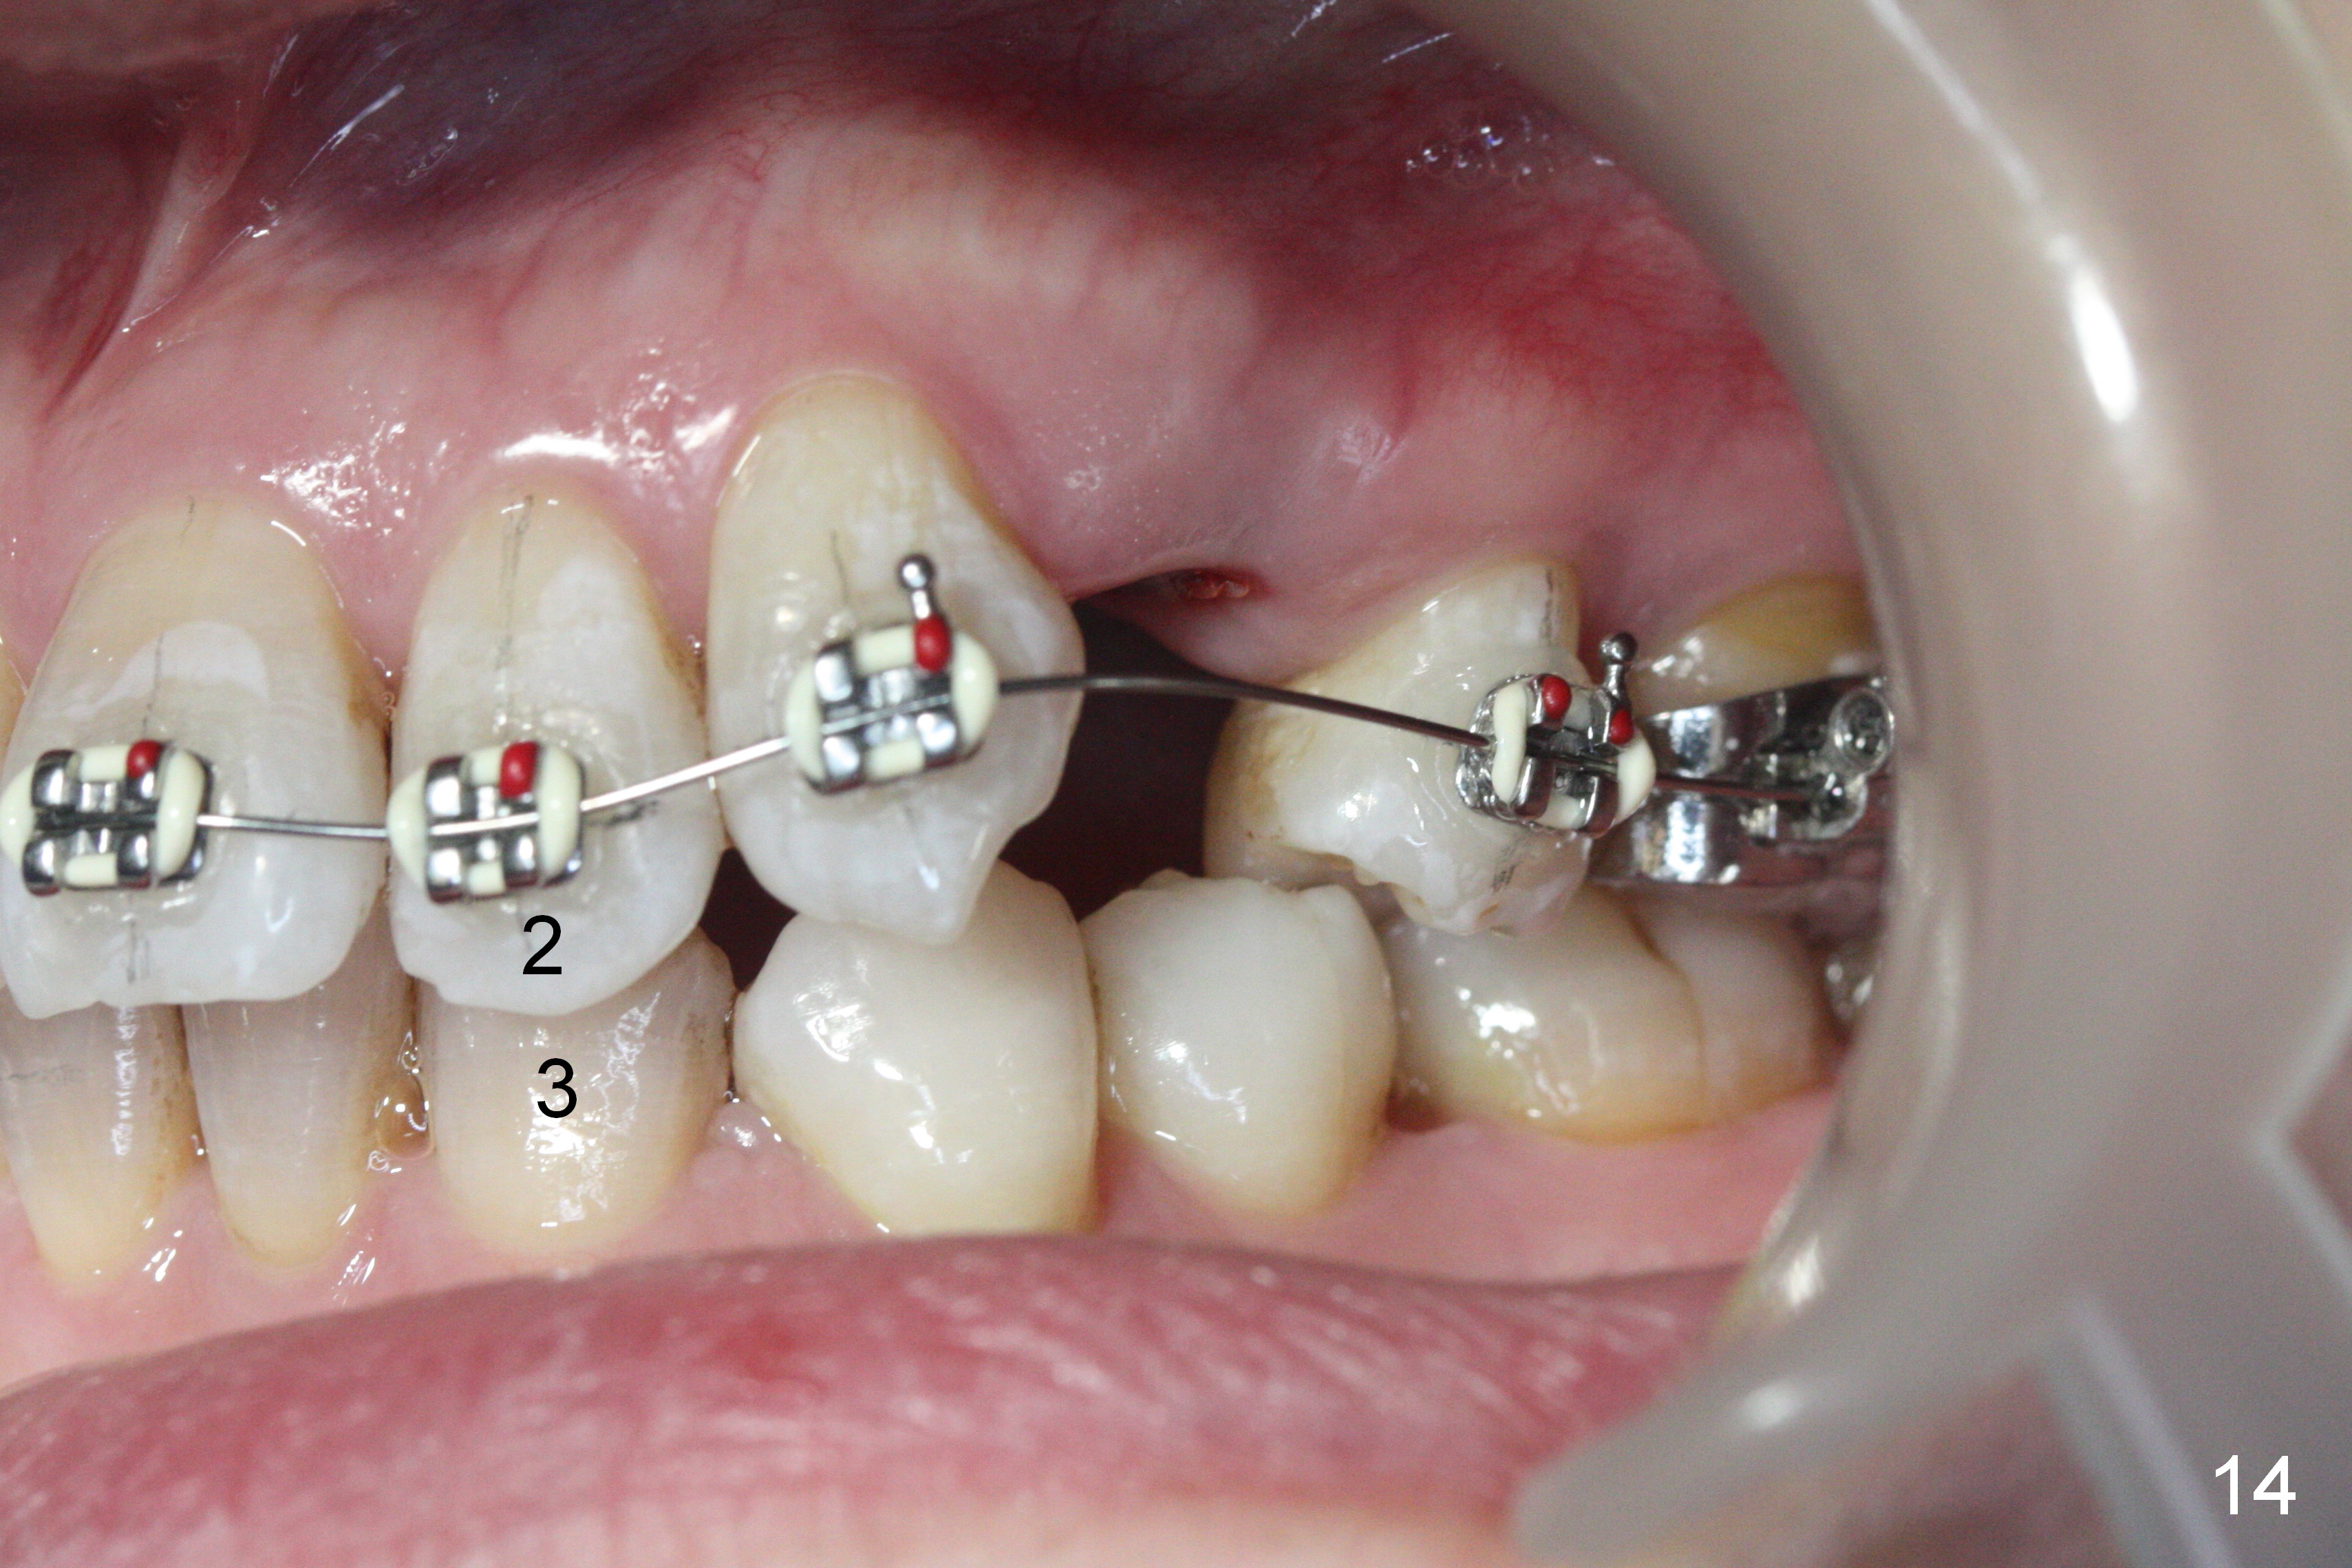

Since U2s are palatally inclined, there is no enough space to place brackets on L3 (Fig.12-14). Lower bracketing is postponed. U4s are extracted 3 days earlier.

Fig.15-17 are taken nearly 2 months post banding. The upper 16 niti is still not fully engaged. Two weeks later, lower brackets are placed with 12 niti wire and occlusal composite (Fig.18-20). Overjet is excessive (Fig.19). Consider distalizing the upper anterior teeth when the upper arch wire changes to a rectangular one.

The rotation of the upper canines is not corrected much in the next 3.5 months (Fig.21, as compared to Fig.18). Distalization of the upper right canine is implemented by power chain, but this is not sufficient because of the anterior deep bite. Note the tension of 18 niti wire between LR 3 and 4 (^). Mini implants are going to be placed mesial or distal to L3s (Fig.22,23 circles) to intrude the lower anterior teeth with elastic or power chain (Fig.23 red line, 24 black area). The upper anteriors will have space to be distalized (Fig.24 arrow). If necessary, proximal reduction will be accomplished at LR3 (extra wide, Fig.25 black outline) for further overjet correction (arrows).